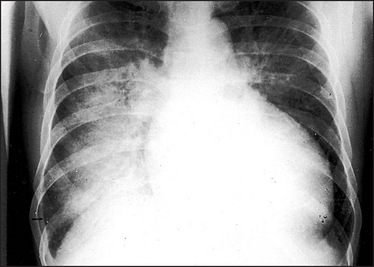

Figure 8.5 Alveolar pulmonary oedema When the pulmonary venous pressure reaches 30 mmHg, oedema fluid will pass into the alveoli. This causes shadowing (patchy to confluent depending on the extent) in the lung fields. This usually occurs first around the hila and gives a bat’s wing appearance. These changes are usually superimposed on the interstitial oedema. A lamellar pleural effusion (arrow) is seen at the right costophrenic angle where Kerley ‘B’ lines are also evident.